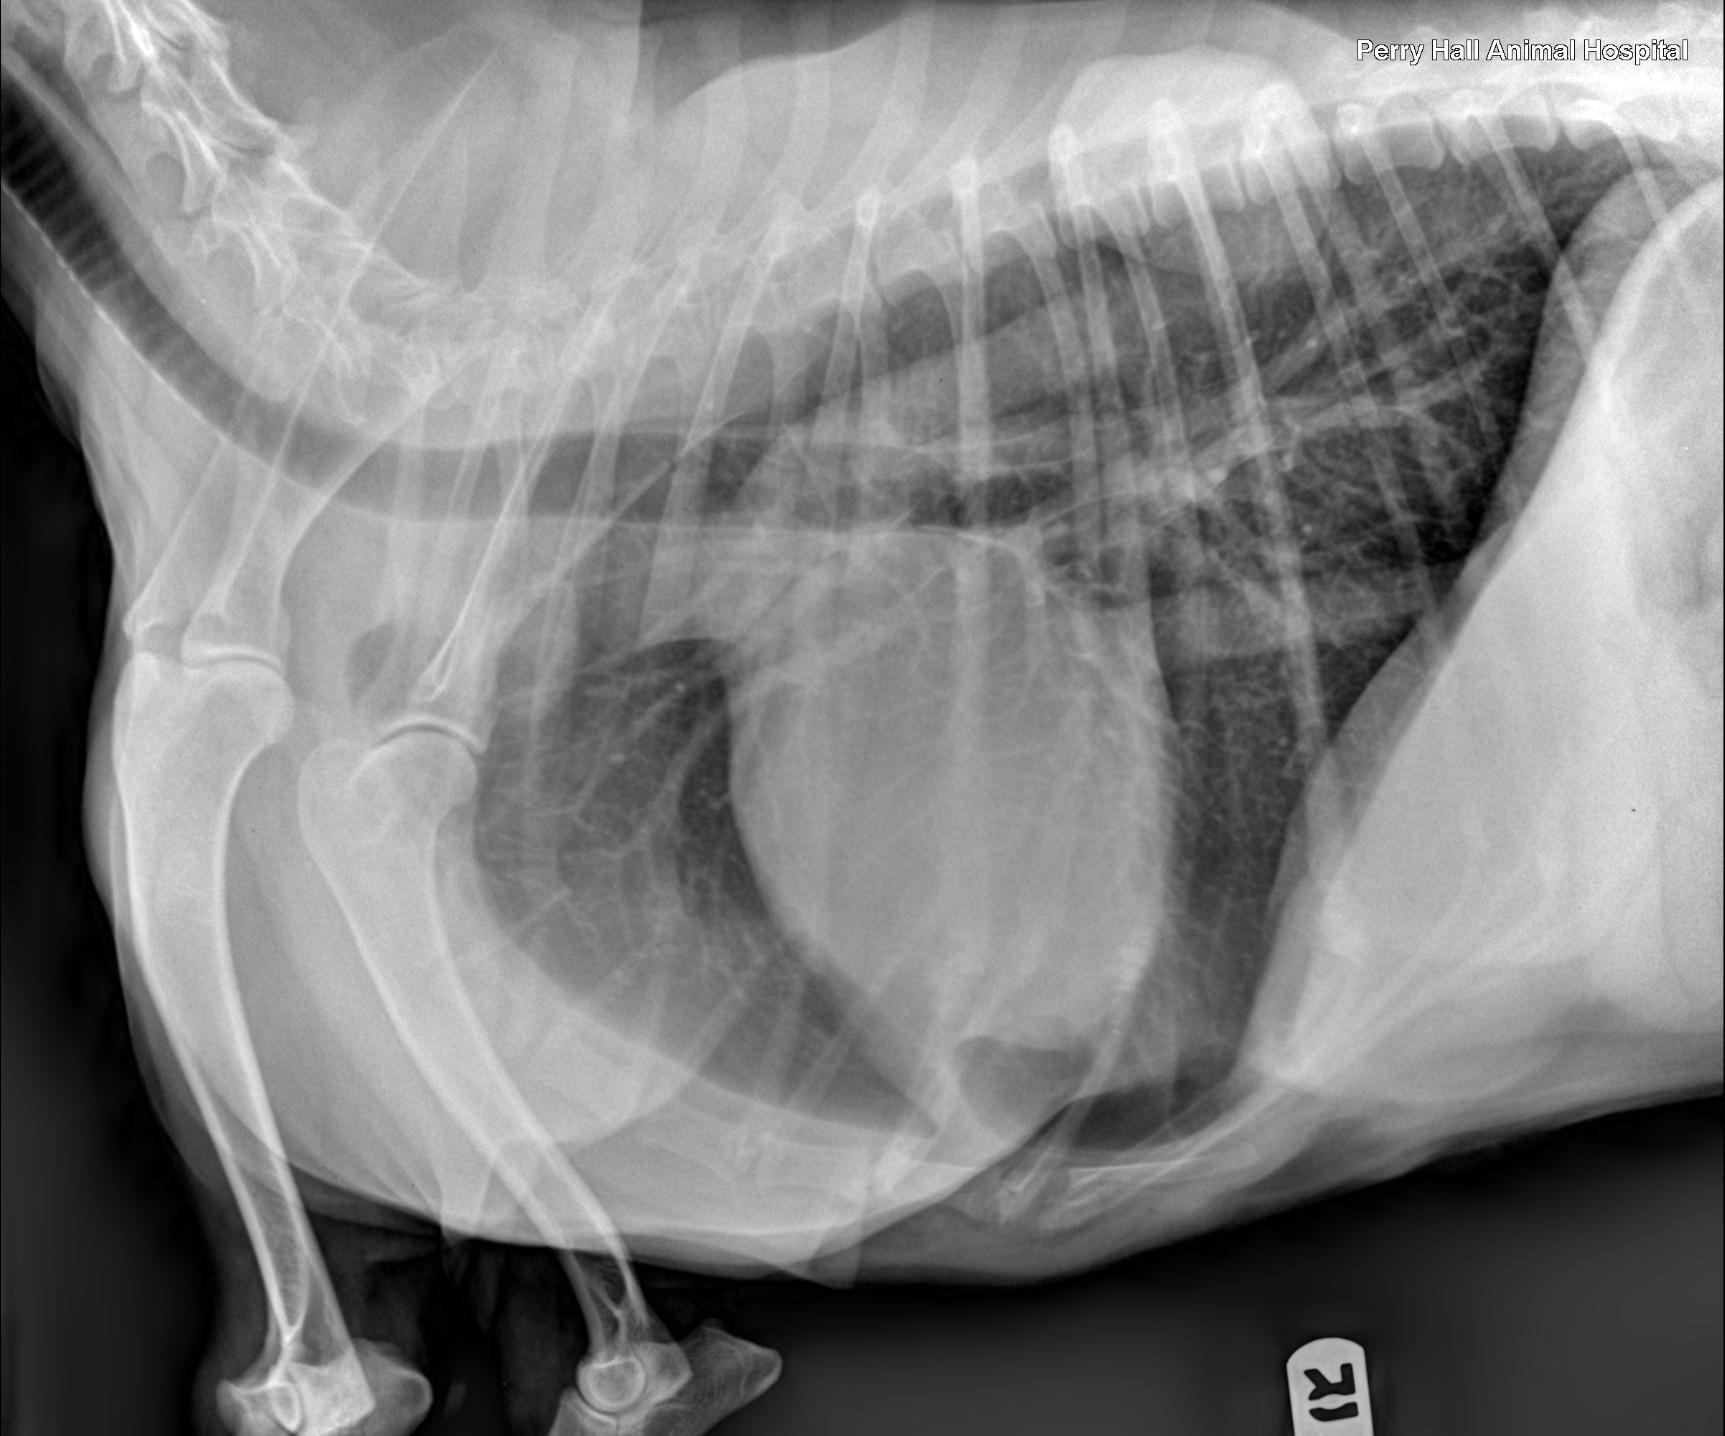

Rads of thorax, right lateral, left lateral and VD: The degree of inspiration was moderate. Osseous structures are within normal limits. Extrathoracic soft tissue structures showed the cervical esophagus was mildly dilated with gas. A subcutaneous, well delineated soft tissue opaque mass lesion measuring 6cm, and a lipoma measuring 10cm were seen along the right lateral chest wall. Intrathoracic structures showed there was an incidental redundant tracheal membrane. The course of the trachea was normal. No mediastinal widening was noted. The cardiac silhouette was small. There was no abnormal prominence of the major vessels. The caudal vena cava was thin. The pulmonary vessels were thin. There was an ovoid, soft tissue, opaque nodule level with the first intercostal space measuring approximately 3cm in diameter. This nodule was visible on both left- and right-lateral views and appeared to be associated with the right cranial lung lobe on the ventro dorsal view. The pulmonary parenchyma showed a mild generalized bronchointerstitial pattern.

The radiographic findings suggest a neoplastic interstitial nodule within the right cranial lung lobe. The location of the nodule is not typical for a primary neoplasia of the lung. Therefore next to a primary neoplasia metastase(s) of another primary tumor have to be considered. There is a lipoma and a subcutaneous soft tissue neoplasia on the right chest wall. The mild bronchointerstitial pattern likely is an age related finding. The potential for current bronchitis is low. The radiographs further show microcardia and under-perfusion of the lung, both of which indicate hypovolemia. There is no radiographic evidence for cardiac disease.